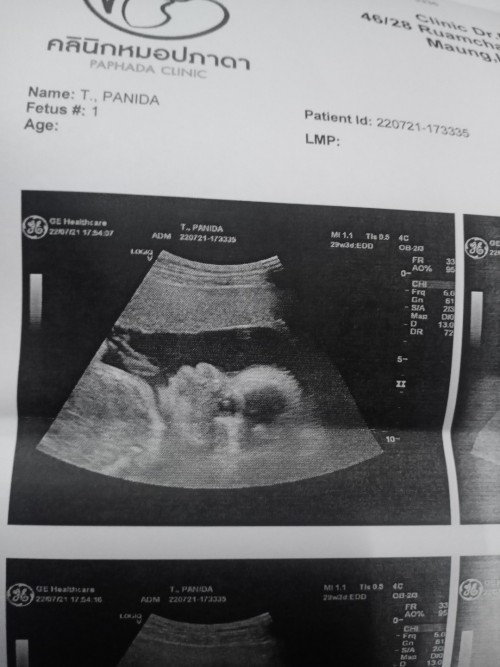

ซาวด์ตอน 28w 4d ตอนนี้ 30w แล้วค่ะ🥰